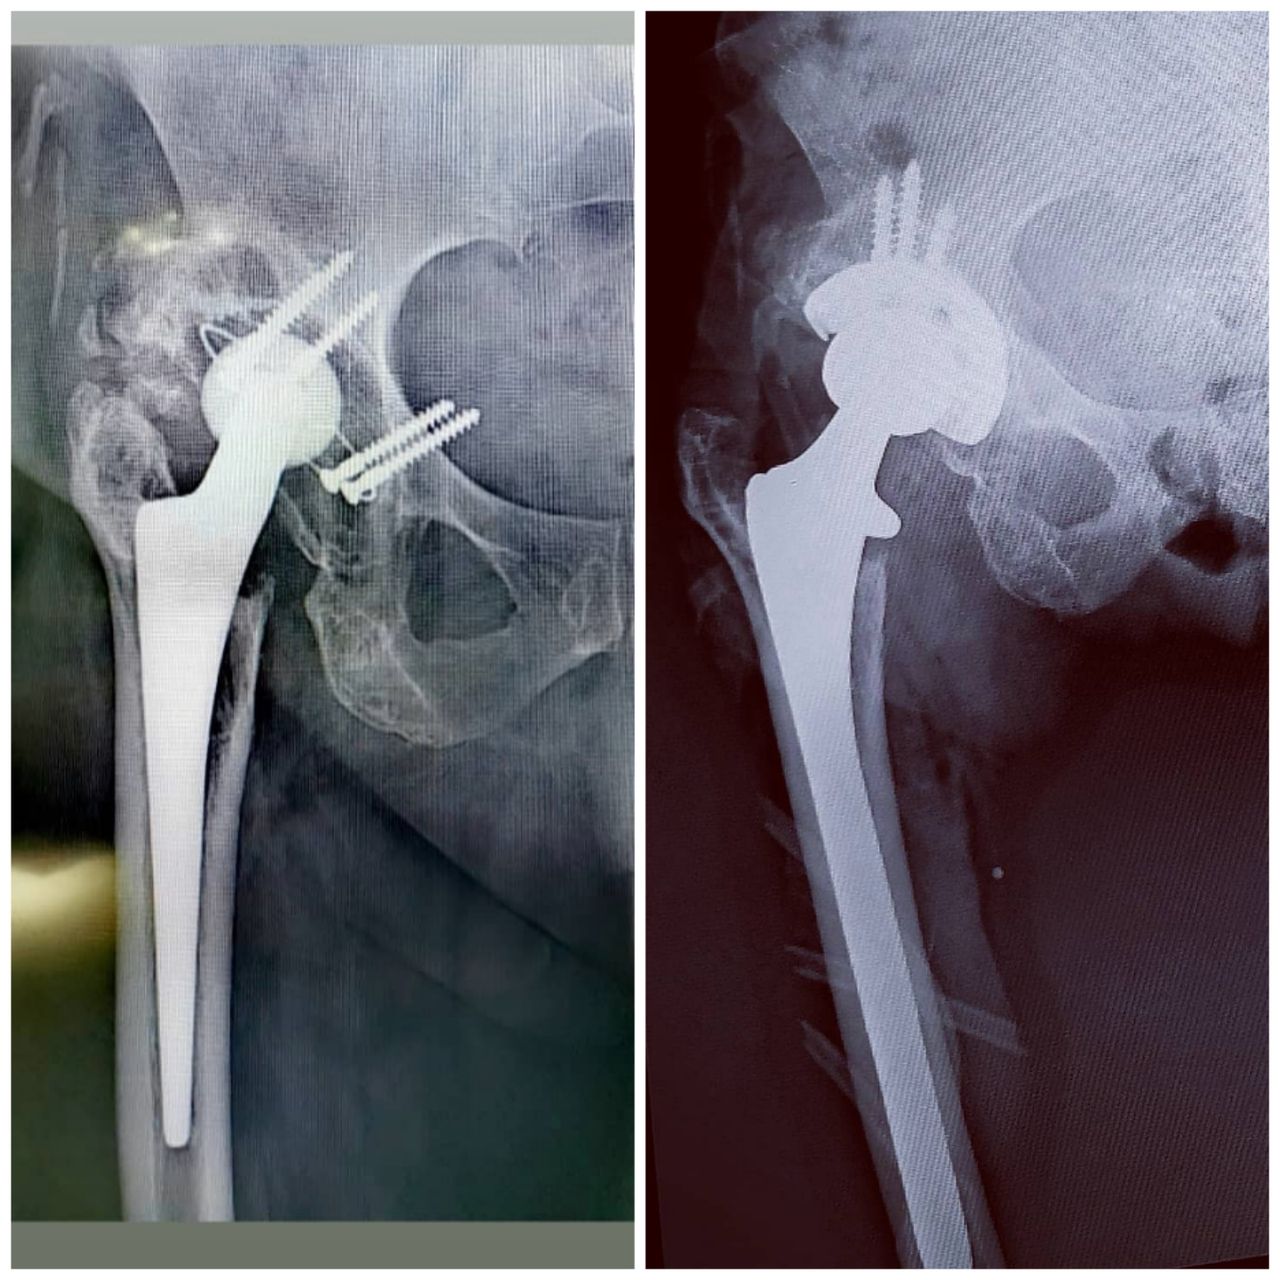

2. ALTA ESPECIALIDAD EN REEMPLAZOS ARTICULARES (PROTESIS DE CADERA, RODILLA Y HOMBRO)

• Reemplazo articular de cadera